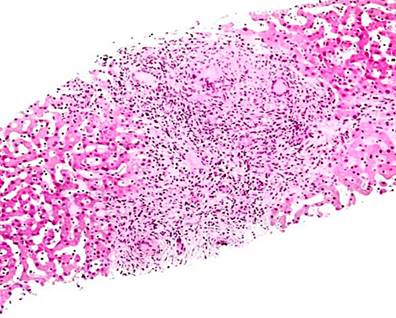

Three greyish-brown elastic fragments with whitish nodules, of which the largest measures 1.6 x 1 x 0.5 cm and the smallest 0.8 x 0.3 cm, were sent to the laboratory. The specimen was fully processed, and histochemical stains (reticulin, periodic acid Schiff [PAS], and Masson’s trichrome) were performed for microscopic evaluation.

In the microscopic evaluation, hepatic tissue with alterations of the standard architecture was seen due to an extensive area of caseation necrosis. Outside, epithelioid cells, Langerhans-type giant cells, and fibrosis were found. In addition, a remnant of hepatocytes with distorted architecture and portal spaces having a fibrous expansion, hydropic degeneration, and sinusoidal congestion was detected. In some areas, there was ductal proliferation. The conclusion of the liver biopsy indicated a granulomatous inflammatory process with caseation necrosis compatible with M. tuberculosis. Figure 5 shows a representation of the histological section. As a result, the pathology department suggested correlating the histopathological findings with the patient’s symptoms.

Figure 5 Histological section of liver tissue with giant cell granuloma. Source: Themes U. Mycobacterium tuberculosis11.